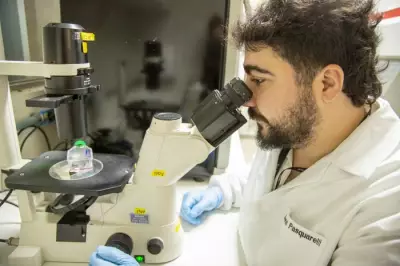

A meningite é uma inflamação das meninges, que são as membranas que envolvem todo o sistema nervoso central. Essa condição pode ser causada por micro-organismos como bactérias e vírus, além de alergias a medicamentos, câncer e outros agentes. Embora os sintomas iniciais possam ser confundidos com os de uma gripe comum, as sequelas da meningite são graves e a doença pode ser fatal.

Além da alta taxa de mortalidade, as complicações incluem surdez, perda dos movimentos e danos ao sistema nervoso. As crianças representam a faixa etária mais afetada, e os pacientes geralmente necessitam de acompanhamento médico por pelo menos seis meses após o diagnóstico. No Brasil, a meningite é considerada uma doença endêmica, com casos ocorrendo ao longo de todo o ano.

Transmissão e sintomas da meningite bacteriana

Conforme explica o Ministério da Saúde, a meningite pode ser causada por bactérias, vírus, fungos e parasitas. A transmissão ocorre quando pequenas gotas de saliva de uma pessoa infectada entram em contato com as mucosas do nariz ou da boca de um indivíduo saudável, por meio de tosse, espirro ou secreções respiratórias. É importante ressaltar que essa transmissão requer contato direto, íntimo e frequente com a pessoa doente.